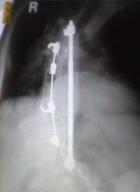

Harrington rods

X-ray after rods were

placed in my back

During surgery, two Harrington rods were attached to vertebrae in my back

to immobilize the curving area of my spine.